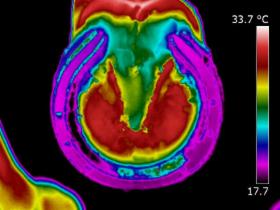

| DISTAL LIMB

| Thermography can point to potential conditions through changes in heat patterns, before the horse shows any clinical signs of injury. It can also reveal hidden signs that other diagnostic tools cannot. It gives us information we didn't know, we didn't know.

| | |  | | | I am very interested in the distal limb and thermography can be used to provide

you and your professional team additional information about conditions such as navicular syndrome,

laminitis, abscesses and corns. Importantly, it can give us information regarding hoof balance and weight-bearing. Hoof balance, often over looked, is a significant influence in the cause of lameness problems not only locally in the foot but throughout the musculature of the body through compensatory issues.